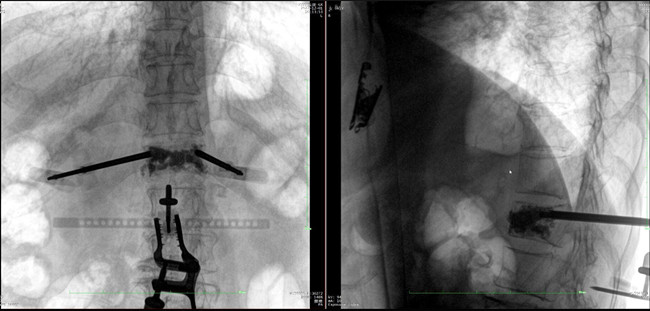

在病人體表切開一個(gè)長1-2cm的創(chuàng)口,沿骨科機(jī)器人的機(jī)械臂定位點(diǎn)方向?qū)⒖耸厢槍?dǎo)向套筒,通過創(chuàng)口送至病灶椎體處,并沿套筒方向打入克氏針進(jìn)行定位。沿導(dǎo)針插入工作套管,取出導(dǎo)針,完成球囊擴(kuò)張后,通過骨水泥注入器準(zhǔn)確地在骨折部位緩慢注入骨水泥,幫助其恢復(fù)椎體的形狀和強(qiáng)度。

*骨水泥置入效果良好